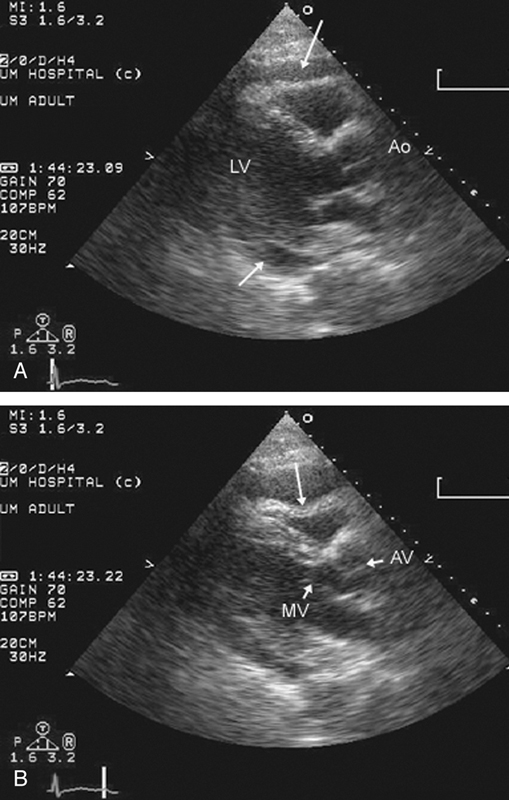

فحوصات تشخيصية لبعض امراض القلب والشرايين التاجية